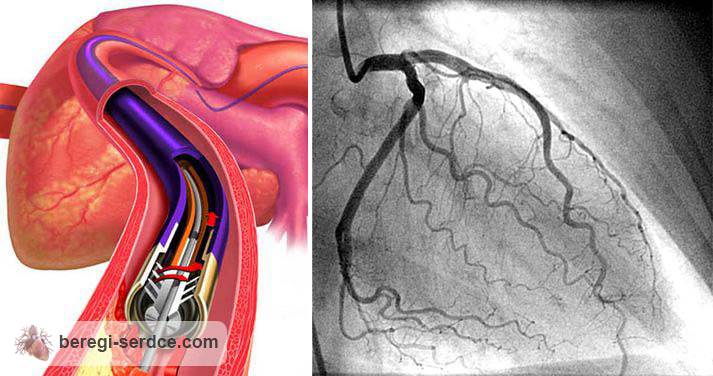

Стентирование коронарных артерий

коронарография изнутри

Стентирование коронарных артерий: как тонкая трубочка меняет судьбы пациентов?